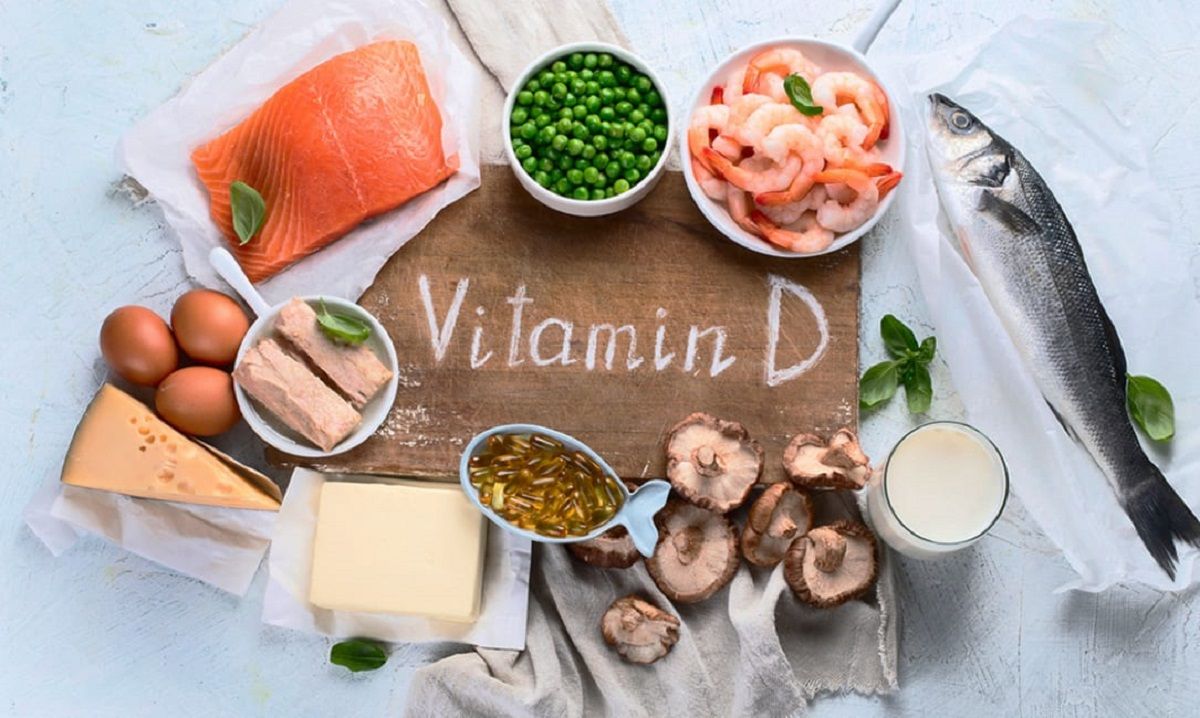

Lipsa de calciu și vitamina D

Fără îndoială, obținerea suficientă de calciu reduce riscul de fractură. Cantitatea recomandată de vitamina D este de 600 UI pe zi până la vârsta de 70 de ani și 800 UI după 70 de ani. Unii oameni pot avea nevoie de o cantitate mai mare pentru a atinge un nivel bun de vitamina D în sânge. Poate fi dificil să-l obții din alimente, așa că te poți baza și pe suplimente de vitamina D.